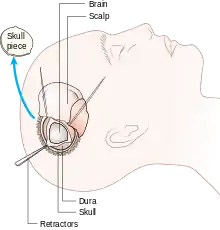

Human craniotomy is usually performed under general anesthesia but can be also done with the patient awake using a local anaesthetic; the procedure, typically, does not involve significant discomfort for the patient. In general, a craniotomy will be preceded by an MRI scan which provides an image of the brain that the surgeon uses to plan the precise location for bone removal and the appropriate angle of access to the relevant brain areas. The amount of skull that needs to be removed depends on the type of surgery being performed. The bone flap is mostly removed with the help of a cranial drill and a craniotome, then replaced using titanium plates and screws or another form of fixation (wire, suture, etc.) after completion of the surgical procedure. In the event the host bone does not accept its replacement, an artificial piece of skull, often made of PEEK, is substituted. (The PEEK appliance is routinely modeled by a CNC machine capable of accepting a high resolution MRI computer file in order to provide a very close fit, in an effort to minimize fitment issues, and therefore minimizing the duration of the cranial surgery.)